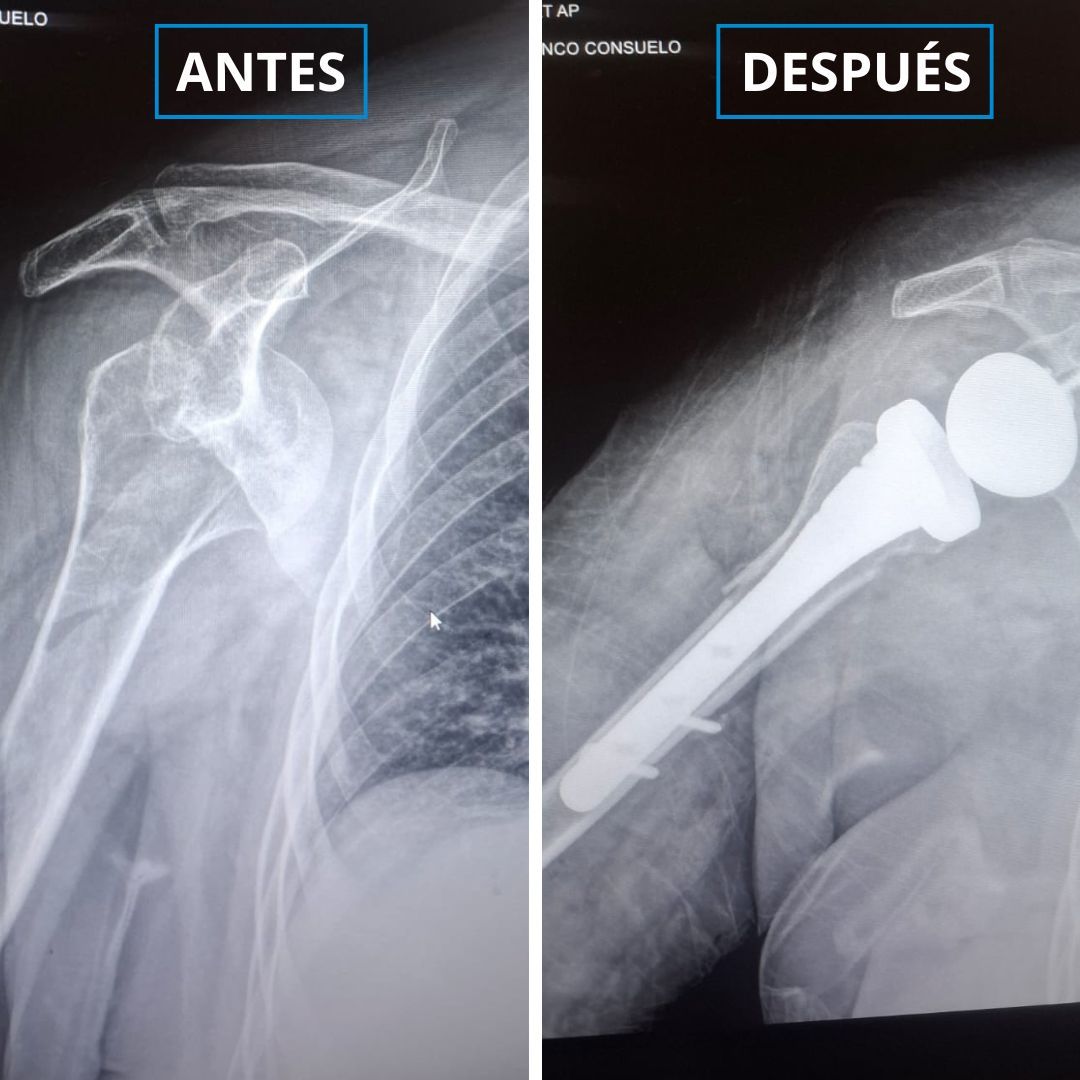

Tristán sufrió una fractura osteoporótica del húmero, que es el hueso que conecta la escápula con antebrazo. Esto implicaba que no podría hacerse una reconstrucción habitual en casos como ese porque su hueso se había fracturado en muchos pedazos.

El coordinador del Servicio de Traumatología del hospital Negreiros, Víctor Bolívar, explicó que "no era viable" hacer una cirugía con placas y tornillos, por lo que "se optó por la colocación de una prótesis reversa de hombro, una de las más modernas que existe en el mundo", recoge el Gobierno peruano en su portal web.

Bolívar, conocido como 'doctor huesos', explicó que la prótesis, llevada de EE.UU. especialmente para la cirugía, es la primera en su tipo colocada en Perú. Con ello, se espera que la "paciente pueda volver a hacer sus actividades funcionales".